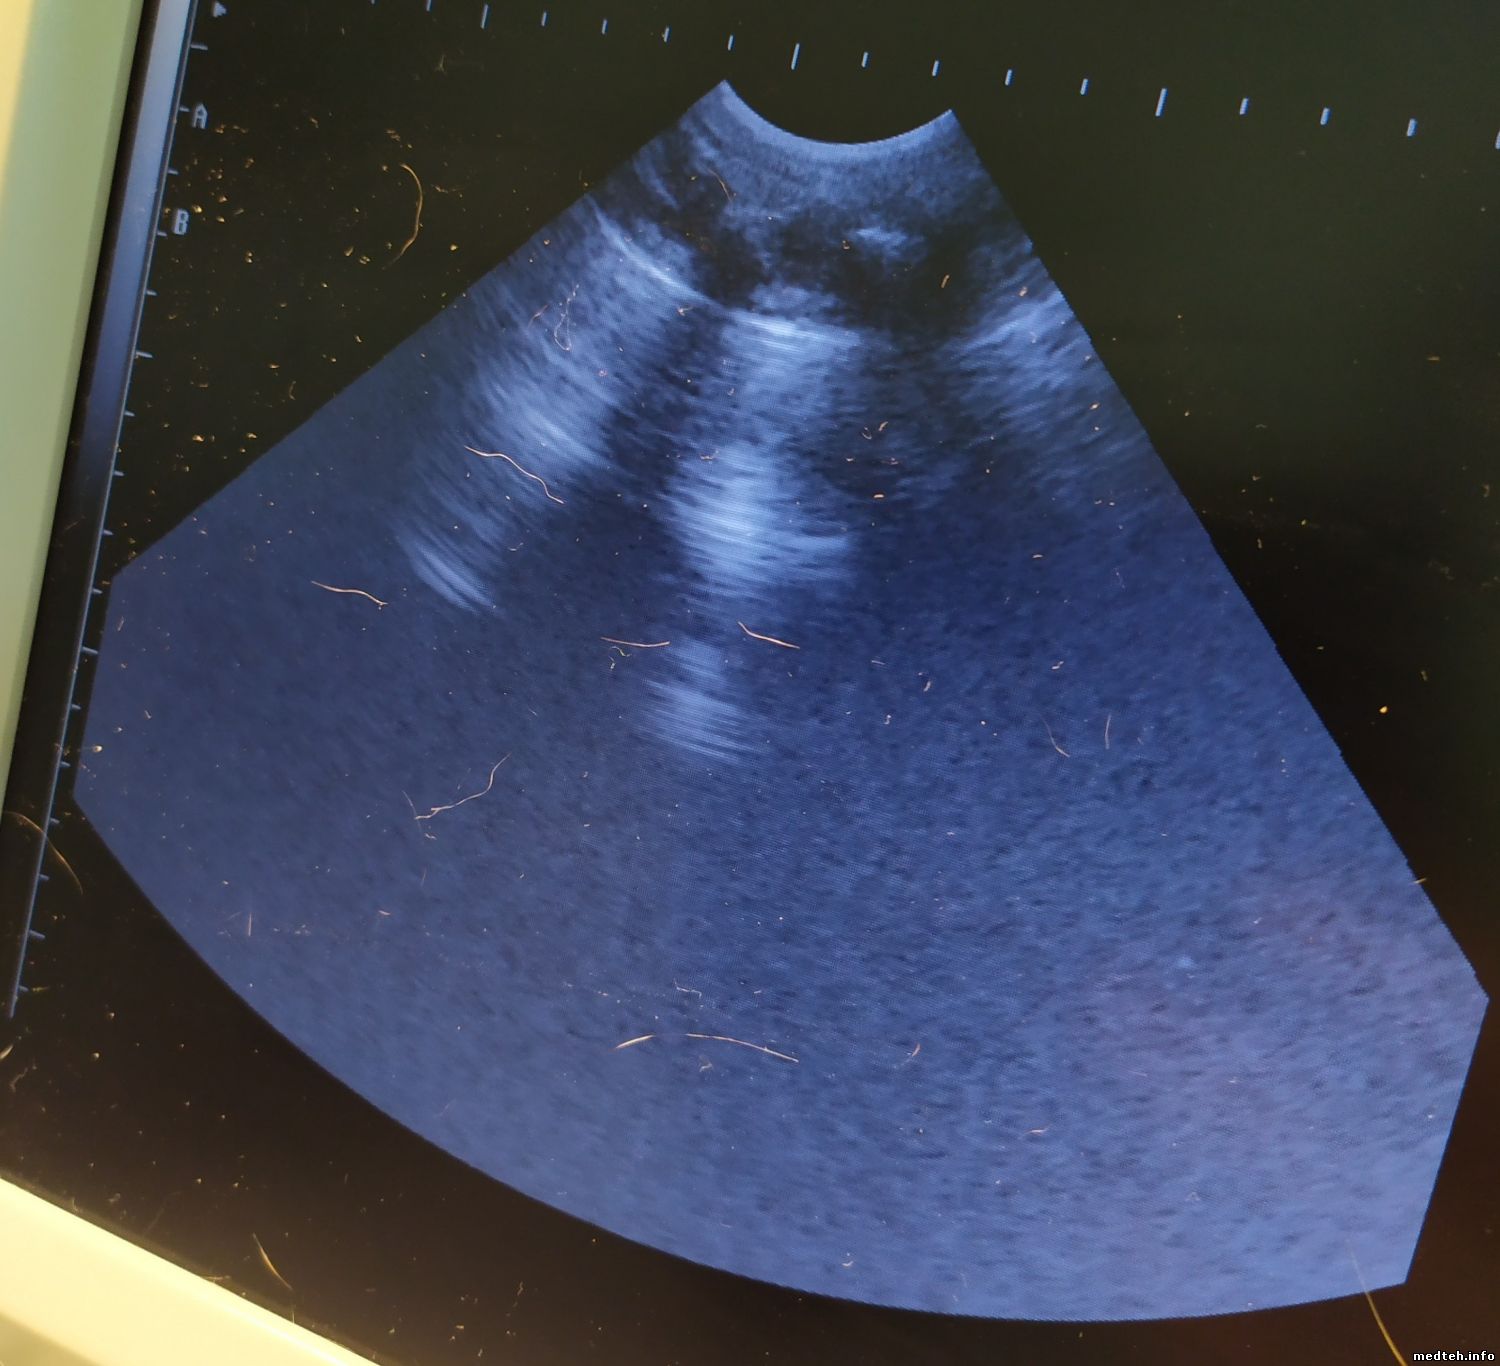

УЗИ ЕМР-860 - портативный аппарат для абдоминальных исследований, гинекологии, урологии, акушерства кардиологии, мелких органов. Производитель: Emperor Medical (EMP), Китай.

Так вот, EMP-860 даёт плохое качество изображения. Подскажите, пожалуйста, в чём может быть проблема и как возможно её решить?

Битых кристаллов на датчике не выявил. На одном фото - пустой датчик, на другом фото - с прижатой рукой.

По картинкам хорошо видно, что проблема все-таки есть. С другими датчиками как?